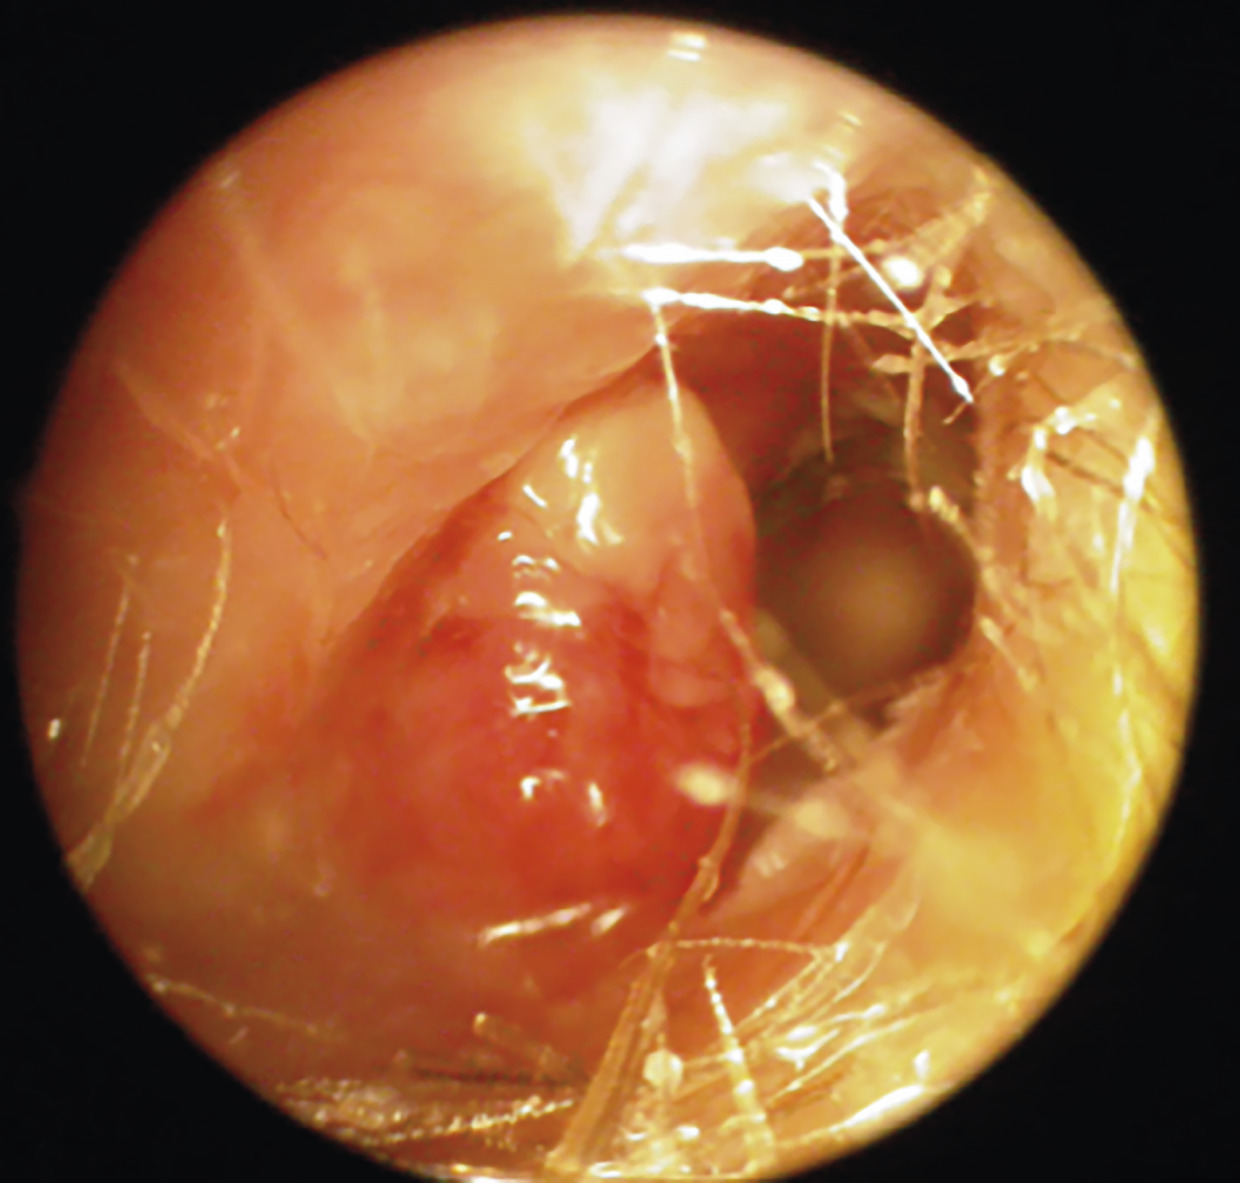

L’examen montre un bourgeon inflammatoire dans le conduit auditif externe, associé souvent à des paralysies des paires crâniennes (nerf facial et hypoglosse).